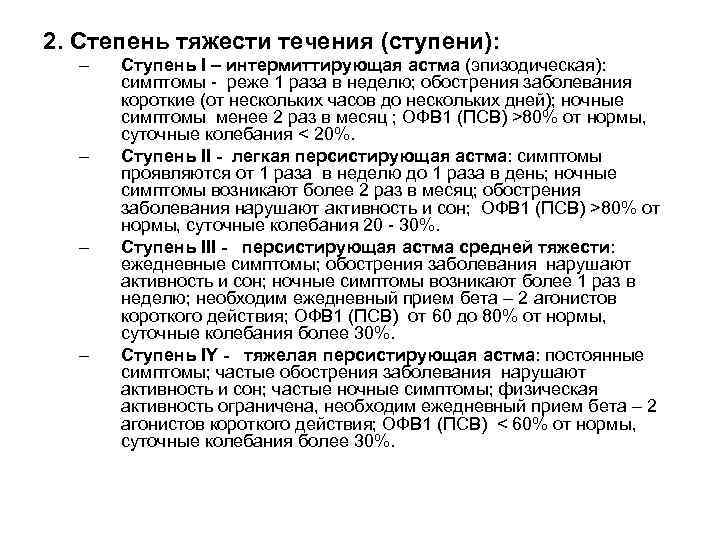

2. Степень тяжести течения (ступени): – – Ступень I – интермиттирующая астма (эпизодическая): симптомы - реже 1 раза в неделю; обострения заболевания короткие (от нескольких часов до нескольких дней); ночные симптомы менее 2 раз в месяц ; ОФВ 1 (ПСВ) >80% от нормы, суточные колебания < 20%. Ступень II - легкая персистирующая астма: симптомы проявляются от 1 раза в неделю до 1 раза в день; ночные симптомы возникают более 2 раз в месяц; обострения заболевания нарушают активность и сон; ОФВ 1 (ПСВ) >80% от нормы, суточные колебания 20 - 30%. Ступень III - персистирующая астма средней тяжести: ежедневные симптомы; обострения заболевания нарушают активность и сон; ночные симптомы возникают более 1 раз в неделю; необходим ежедневный прием бета – 2 агонистов короткого действия; ОФВ 1 (ПСВ) от 60 до 80% от нормы, суточные колебания более 30%. Ступень IY - тяжелая персистирующая астма: постоянные симптомы; частые обострения заболевания нарушают активность и сон; частые ночные симптомы; физическая активность ограничена, необходим ежедневный прием бета – 2 агонистов короткого действия; ОФВ 1 (ПСВ) < 60% от нормы, суточные колебания более 30%.

Степени тяжести